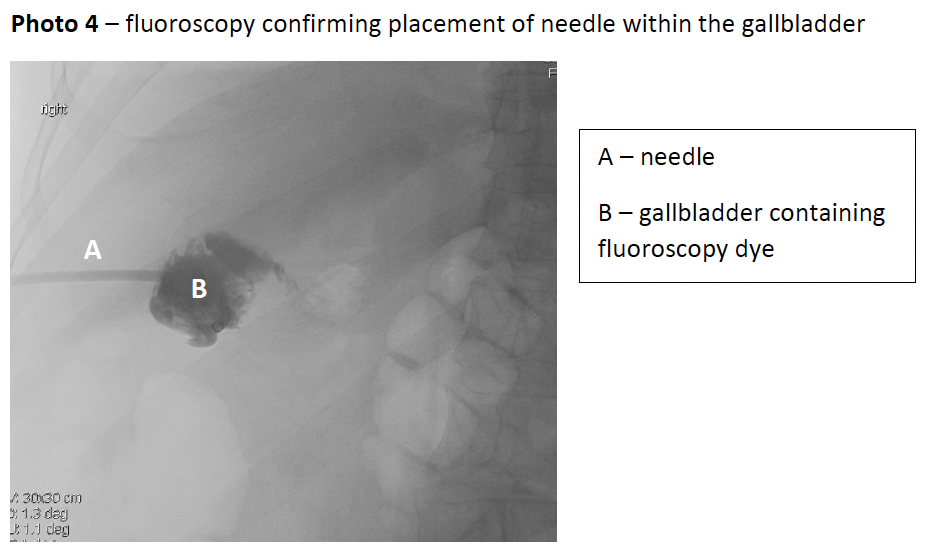

Despite only having ceased clopidogrel for 2 days, due the patient’s deteriorating clinical situation and lack of other options, PCo was performed under ultrasound guidance following a transhepatic approach (photo 3); the position was confirmed using fluoroscopy (photo 4), followed by a 12-French pigtail catheter insertion. Aspirated bile was sent for microscopy/culture/sensitivity which revealed gram-negative rods found to be Klebsiella pneumoniae sensitive to ceftriaxone.